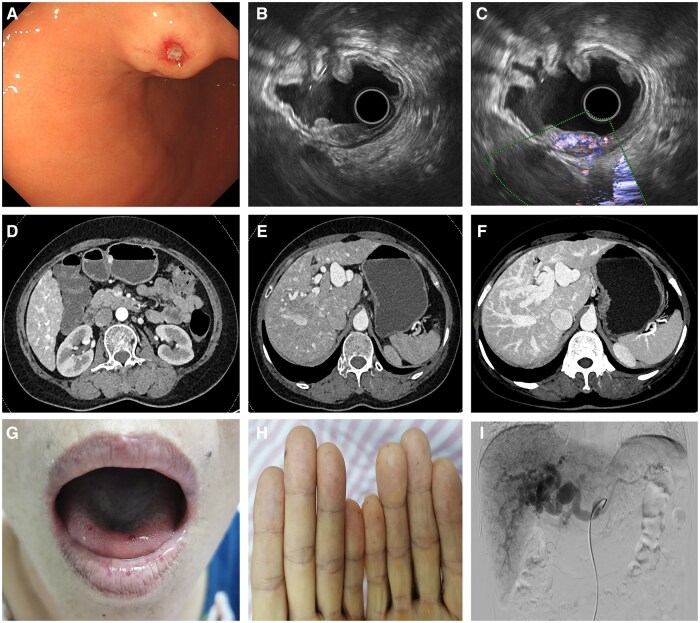

An unusual gastric submucosal prominence diagnosed as hereditary hemorrhagic telangiectasia.

一个不寻常的胃粘膜下突出诊断为遗传性出血性毛细血管扩张。